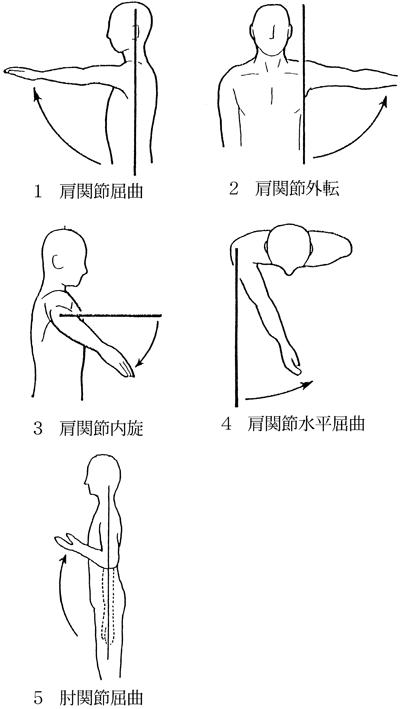

63歳の男性。脳出血による左片麻痺。Brunnstrom法ステージは左上肢Ⅲ、左手指Ⅲ及び左下肢Ⅳ。上肢の分離運動促通を目的とした自主訓練として適切なのはどれか。

1

1

2

2

3

3

4

4

5

5